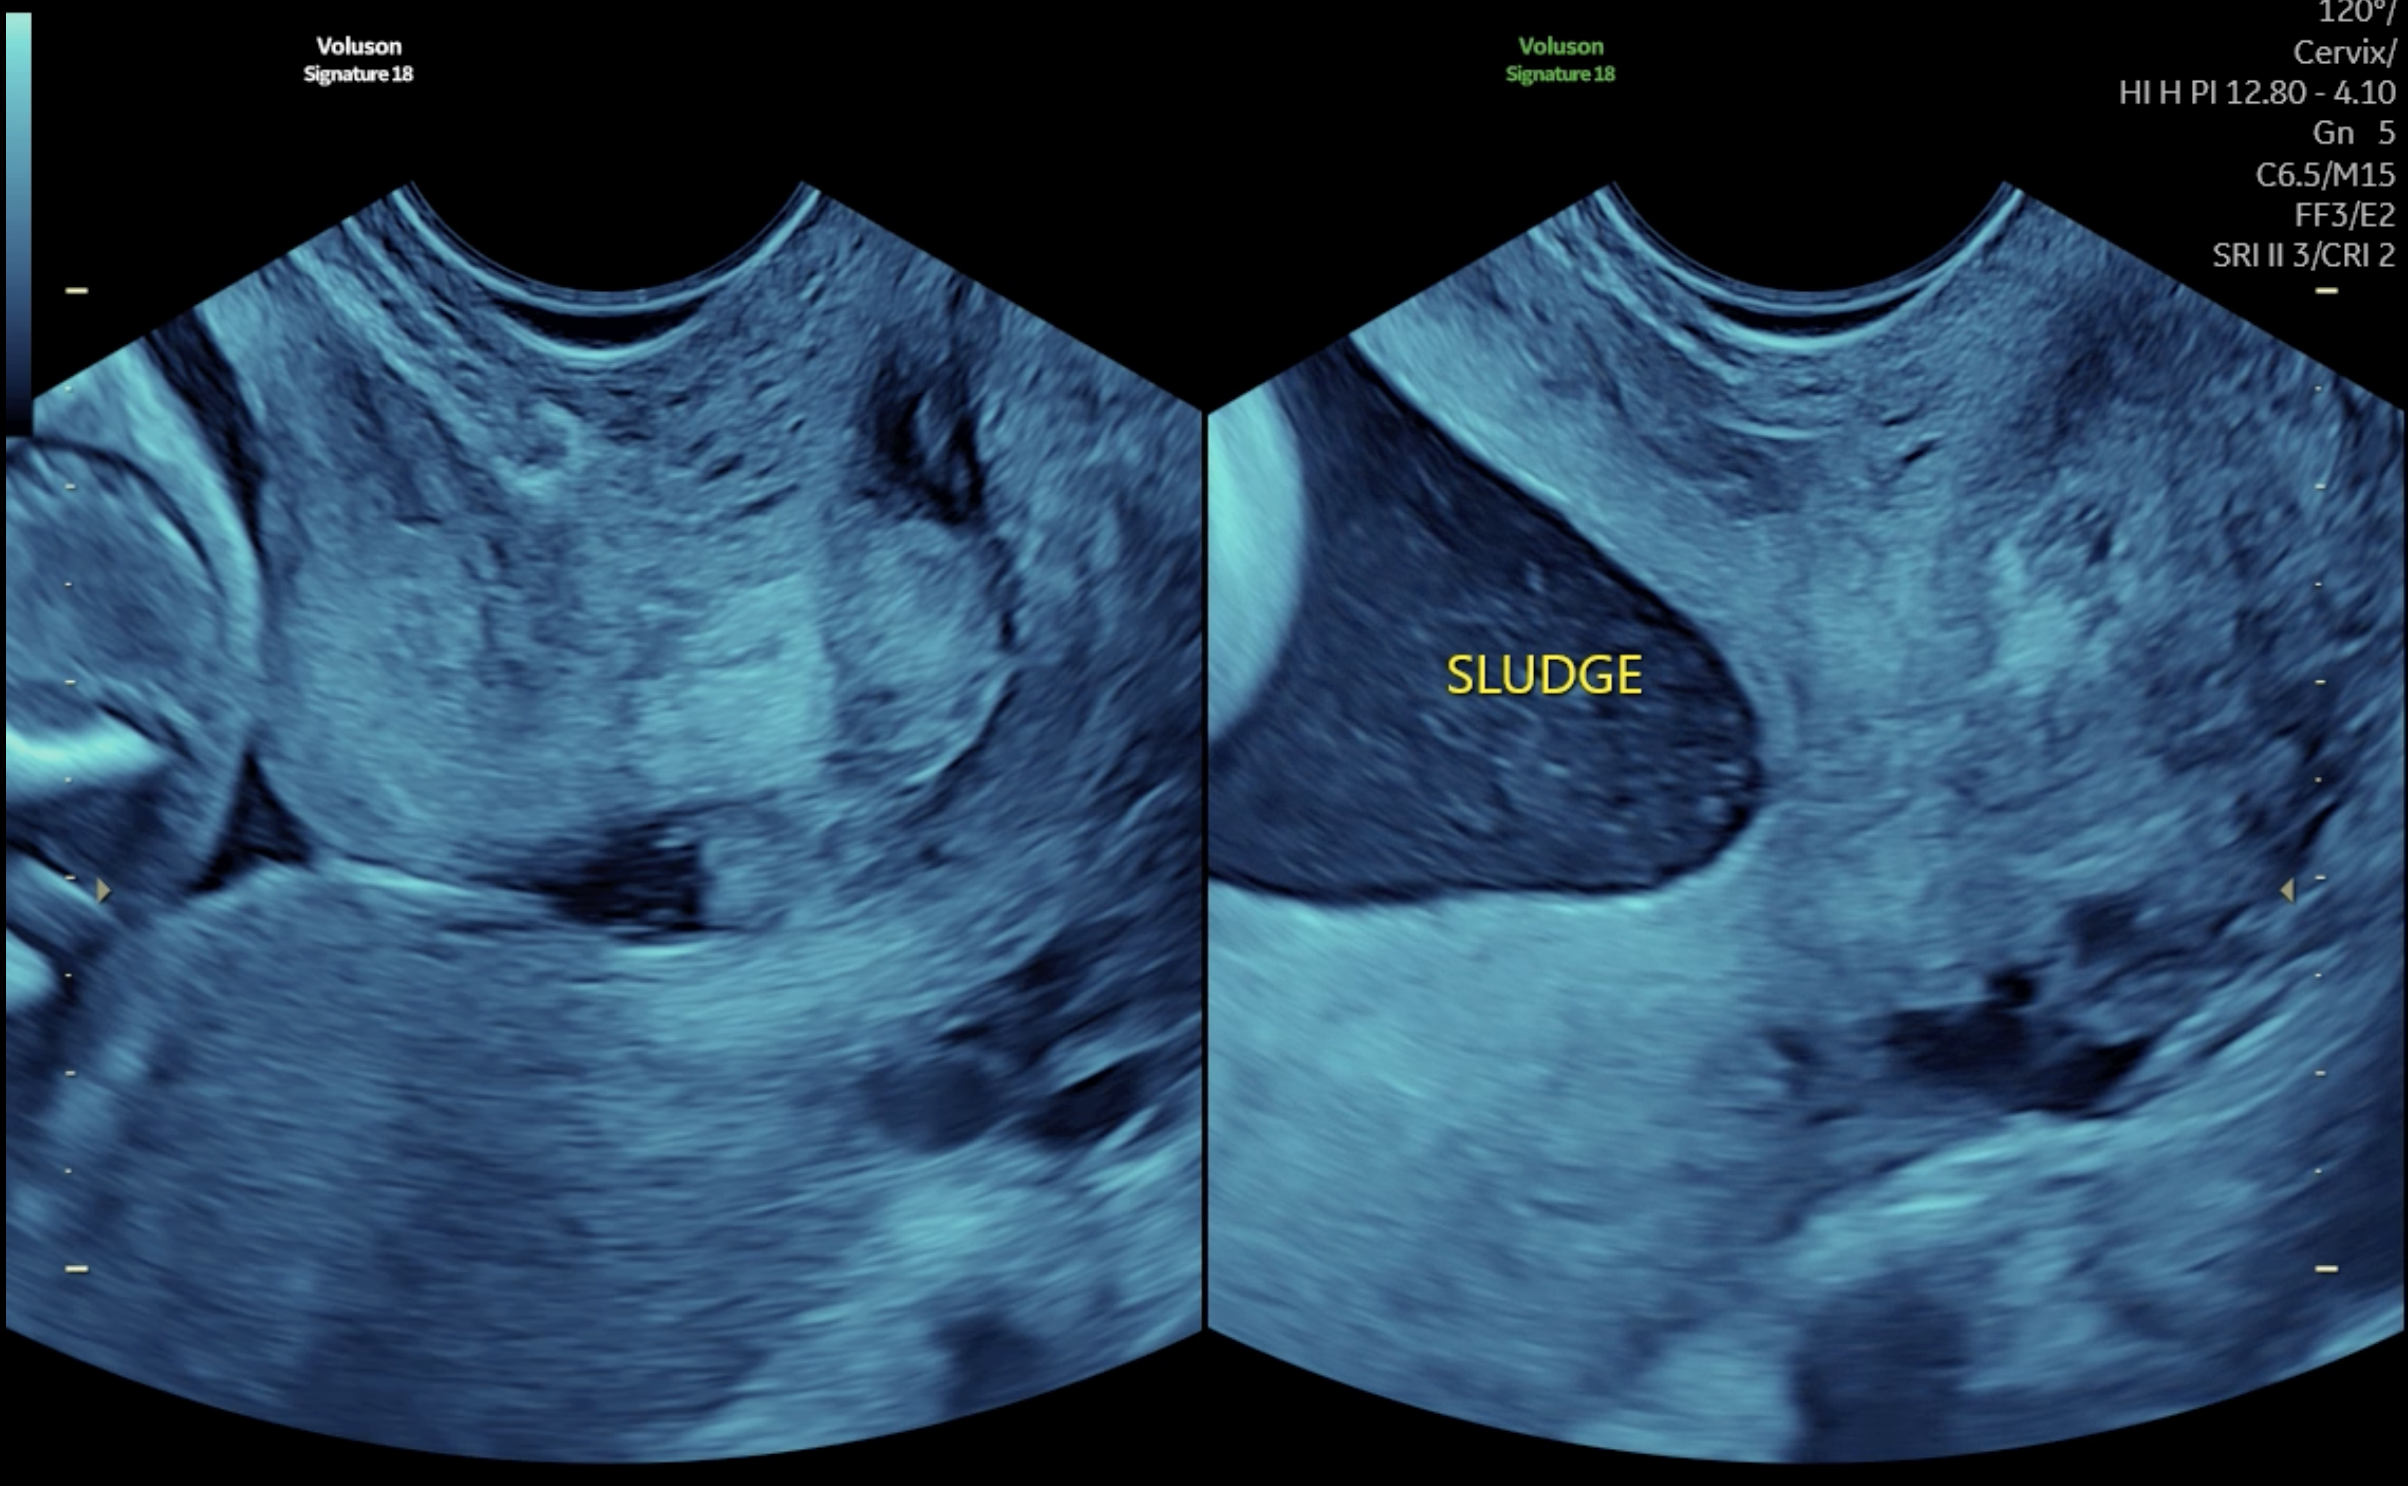

CTC đóng khi không có cơn gò tử cung và mở ra, ngắn lại khi cơn gò xuất hiện

CTC của chị mở ra khi có cơn gò tử cung và đóng lại khi qua cơn gò. Ở thời điểm CTC mở ra, màng ối và nước ối với nhiều cặn ối đã chui vào kênh cổ tử cung. Đây là một tình huống cực kỳ nguy hiểm, nếu không được phát hiện kịp thời thì cổ tử cung sẽ tiếp tục mở ra, ngắn dần và nguy cơ sảy thai trong thời gian ngắn là điều không thể tránh khỏi. Các BS đã khẩn trương tiến hành các thủ tục cần thiết và bệnh nhân được khâu CTC cấp cứu ngay trong ngày.